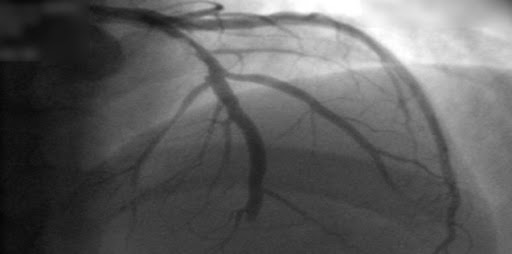

Estudios coronarios en la cardiopatía isquémica estable: ¿TC o cateterismo?

Este estudio no encontró diferencia entre mujeres y varones en el beneficio del uso de la tomografía computarizada (TC) en lugar de la angiografía coronaria invasiva como prueba diagnóstica inicial para el manejo del dolor torácico estable en pacientes con una probabilidad previa a la prueba intermedia de enfermedad arterial coronaria. La TC inicial se asoció con menos complicaciones importantes relacionadas con el procedimiento en las mujeres y una frecuencia más baja del compuesto MACE expandido en los hombres.British Medical Journal, 19 de octubre de 2022.

En los pacientes remitidos para cateterismo coronario por dolor torácico estable y con probabilidad intermedia de enfermedad coronaria antes de la prueba, la evaluación inicial por tomografía computada tuvo un riesgo de eventos cardiovasculares mayores similar a los de la evaluación invasiva, pero una menor frecuencia de complicaciones mayores relacionadas con el procedimiento. New England Journal of Medicine, 28 de abril de 2022.

Evaluación con tomografía computada en pacientes con probabilidad intermedia de enfermedad coronaria derivados para angiografía

Sólo el 14% de los evaluados inicialmente con TC requirió angiografía coronaria invasiva; no hubo diferencias clínicas en el seguimiento a 3 años. BMJ, 24 de octubre de 2016